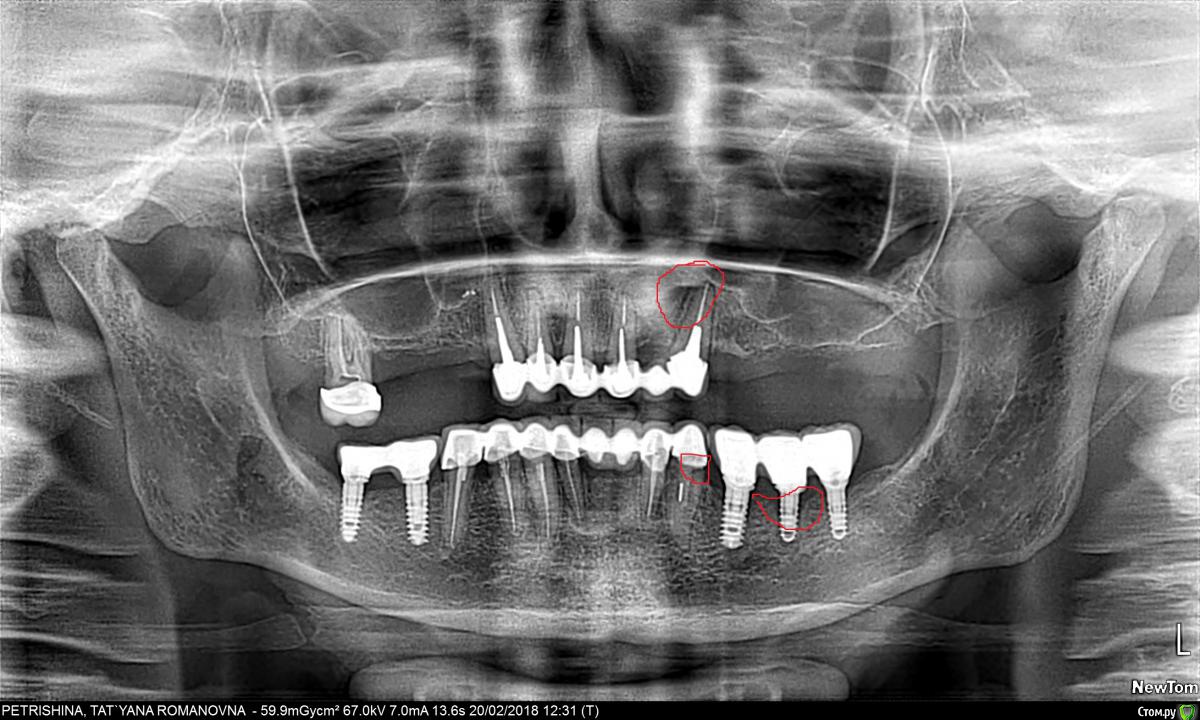

Mars12 Опубликовано 14 марта, 2018 Автор Поделиться Опубликовано 14 марта, 2018 Доброго дня!Помогите разобраться ( обозначила на снимке)Верхний зуб беспокоит, при кусании чувствуется тупая боль(как будто штифт давит на корень)Нижние три имплантата, смущает кость(точнее её нехватка ) Простите за такие вопросы,объём работы большой и деньги немаленькие, ещё нужно делать верхнюю челюсть, поэтому задаю вопросы , доктор на них не может ответить... Ссылка на комментарий

Irouil Опубликовано 14 марта, 2018 Поделиться Опубликовано 14 марта, 2018 Спасибо!С Днём рождения Вас!Здоровья, успехов и всего самого наилучшего!Пятый-это средний, где три имплантата!Спасибо Может быть формируется карман, но тут надо во рту смотреть: по снимкам точно сказать я не смогу. Верхний зуб выглядит нормально, но если беспокоит есть смысл сделать КТ. Возможно что-то панорамный снимок недоговаривает. Ссылка на комментарий

колесников Опубликовано 16 марта, 2018 Поделиться Опубликовано 16 марта, 2018 Средний Имплант ,обозначенный вами, будет причинять дискомфорт,его следует или заглушить или переустановить. Ссылка на комментарий